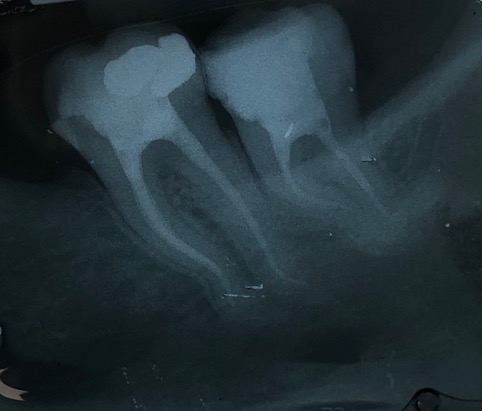

Capita spesso di incontrare denti già devitalizzati in maniera impropria che necessitano, seppur asintomatici, di essere ritrattati per evitare che i granulomi infetti visibili radiograficamente si evolvano riassorbendo tutto l’osso sottostante.